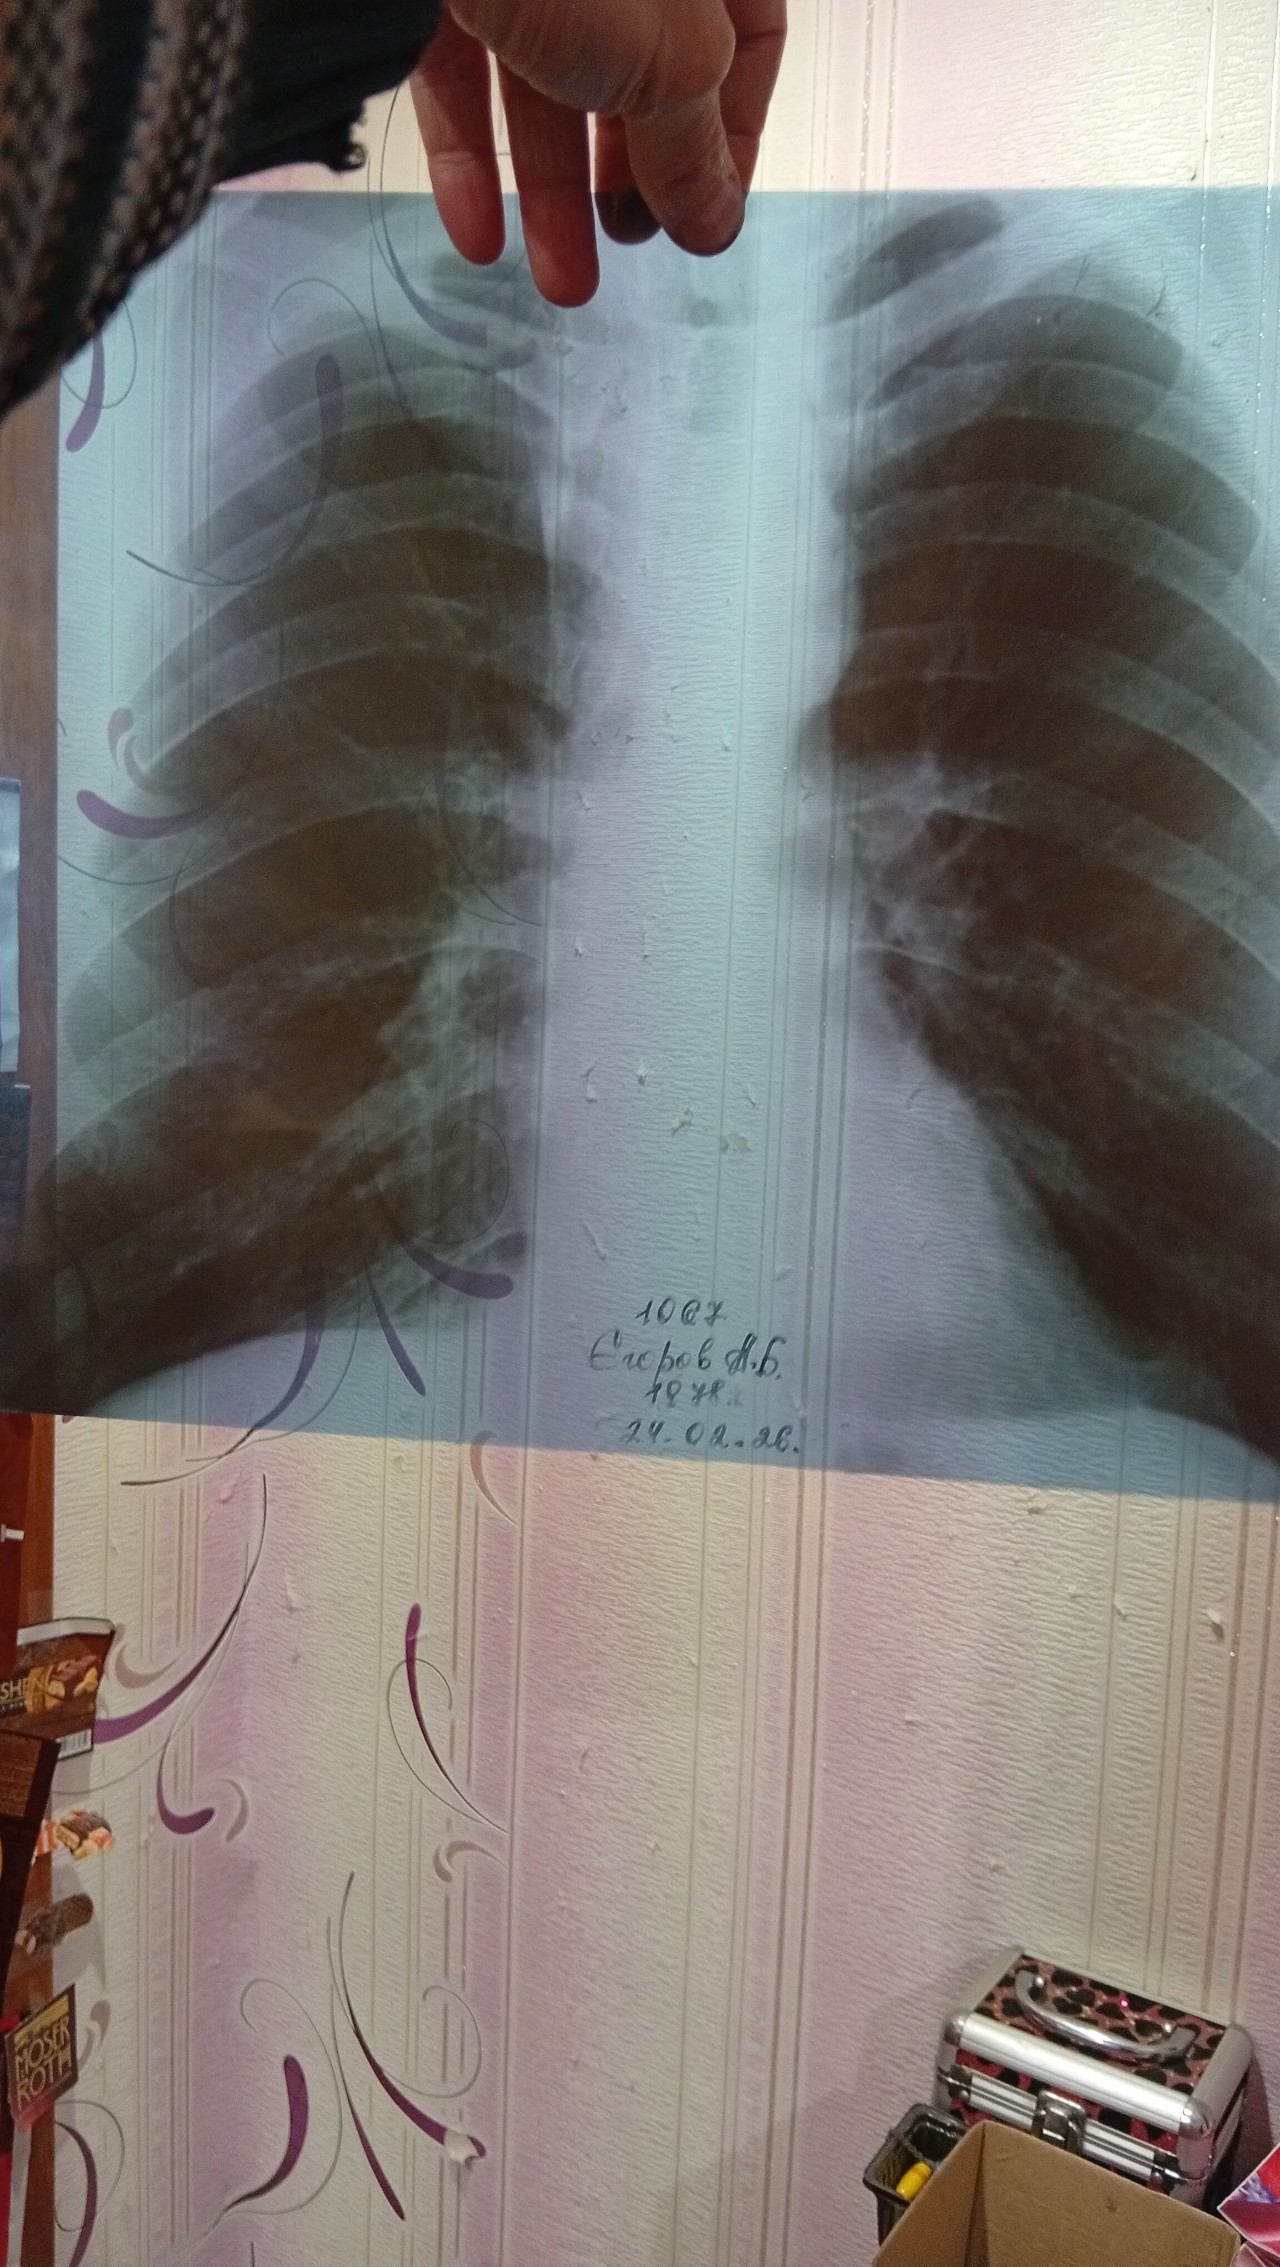

Опис рентгену

Доброго дня, дайте відповідь, що за хвороба по опису рентгену. Корені ущільнені, легеневий малюнок дещо підсилений справа в обл. К/д кута. Серце ьро. Синуст зрізані. Симптоми. Кашель сухий, біль в грудях, задишка, сатурація94-97. Темперптура 36.6.

Описание и клиника соответствует острому бронхиту. На пневмонию не похоже. Что в крови? На какой день заболевания сделан рентген?

Здравствуйте! Признаков пневмонии нет. Какие жалобы на момент исследования и сейчас?

На снимке все нормально, может быть бронхит, его на снимке не видно

При обострении астмы или бронхита лёгкие превращаются в воздушную ловушку: вздохнуть легче чем выдохнуть,. Поэтому за счёт воздуха идёт обеднение рисунка. Признаков пневмонии, то есть затемнения нет